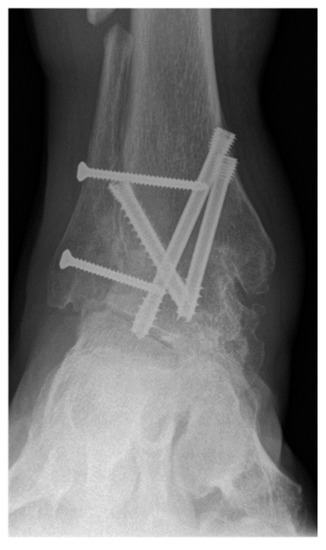

Operative approach, fixation method, choice of allograft/autograft/bone graft substitutes were varied based on surgeon and patient factors. Figure 2 shows radiographs of a typical case in this study in which the distal tibiofibular arthrodesis was included in the construct. In each case the foot was positioned in slight valgus, external rotation, and dorsiflexion and provisionally fixated for fluoroscopic imaging. If the foot position was deemed satisfactory, the tibiotalar joint +/− distal tibiofibular joint were fixated. Final fluoroscopic images were routinely obtained prior to closing the wounds and placing post-operative immobilization with use of a splint or boot. There was not a standardized post-operative protocol, but all patients were instructed to be non-weight bearing for a minimum of 6 weeks after surgery. Generally, patients were followed at 2, 6, and 12 weeks, 6 month, and 1-year intervals.

Figure 4.

A 62-year-old female patient presenting complete union of the tibiotar and distal tibiofibular joints at 4 months follow-up.